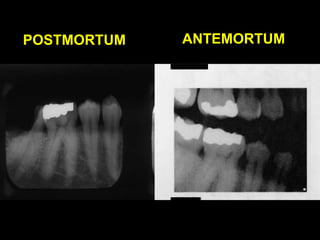

POSTMORTUM

ANTEMORTUM

POSTMORTUM ANTEMORTUM

• A match?

Comparative dental identification Includesfour steps STEP 1: Oral autopsy STEP 2: Obtaining dental records STEP 3: Comparing postmortom and antemortom dental data STEP 4: Writing a report and drawing conclusion